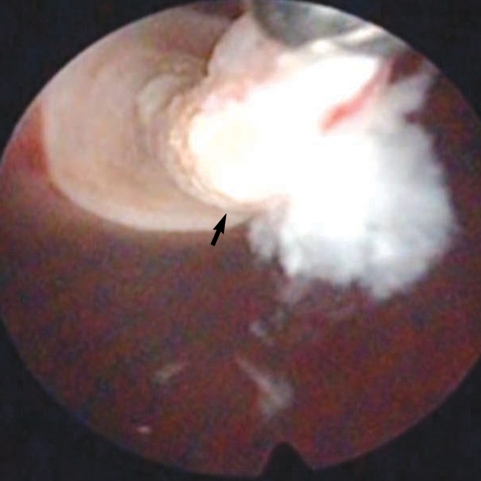

At operation, multiple spargana were found within the mass, around the spermatic cord and scrotal soft tissues (Figs. 1, 2). All identified spargana worms were completely excised. Diagnostic cystoscopy was performed consecutively to evaluate the microscopic hematuria, and a 10-mm sized small nodular mucosal elevation was found in the right side of the dome of the urinary bladder (Fig. 3). Covered mucosa was removed using resectoscope, and a whitish worm-like mass surrounded by granulation tissues was found inside of the nodule (Fig. 4). We tried to remove it by forceps, but it came apart. Histological examinations revealed a foreign body granuloma with a few infiltrates of eosinophils. In a serological test, patient's serum showed a positive reaction to anti-sparganum IgG antibody.

The larval tapeworms were morphologically identified as the spargana of Spirometra erinacei. The worm from urinary bladder was put to a PCR sequencing analysis. The PCR amplification and direct sequencing for the cox1 target fragment (353-bp in length corresponding to the positions 769-1,121 bp of the cox1 gene) were performed using the total genomic DNA extracted from paraffin-embedded samples. The cox1 sequences (353 bp) of the specimen showed 98% similarity to the reference sequences of the Japanese origin Spirometra erinaceieuropaei (GenBank No. AB-278575.1) and 90% similarity with the reference sequence of Spirometra proliferum (GenBank No. AB015753.1).